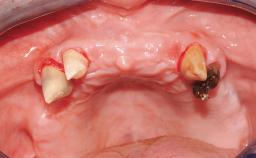

A healthy 31-year-old female patient presented with a failing maxillary left lateral incisor crown. The crown regularly loosened, and the remaining tooth was neither restorable nor rational to treat. The patient had a high smile line, a medium soft tissue biotype with a compromised mesial papilla (shorter than the contralateral one), and a horizontal scar in the buccal soft tissue as a result of past periapical surgery.

| Keratinized Tissue | Minimal (2-4 mm) |

| Soft Tissue Quality | Presence of minimal scars/no inflammation |

| Papilla | Deficient |

| Recession | Absent |

| Interproximal attachment | At CEJ |